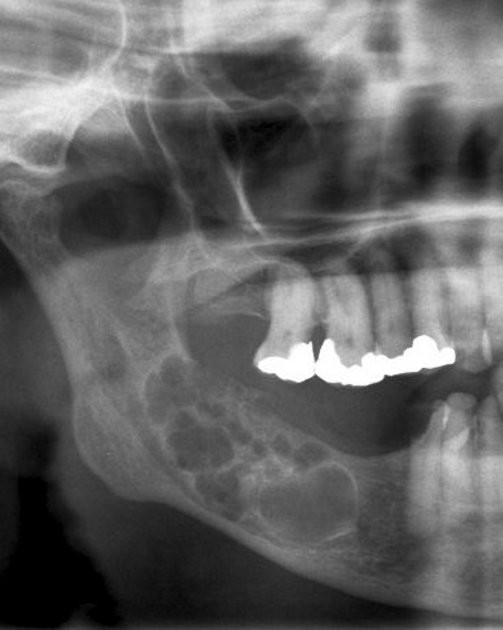

7. (Select ONE correct answer)

What is the most likely diagnosis for this patient?